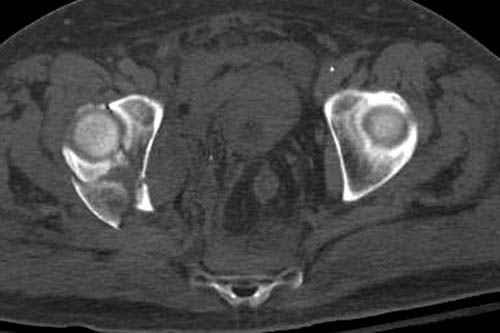

Дополнительно имеется перелом ацетабулума: задняя

колонна с полупоперечным переломом, и переломы костей лица.

На седьмой день зафиксирован перелом ацетабулума через задний доступ. Перед операцией для профилактики DVT, IVC фильтер, также получает Lovenox.

Отправитель: Evgueny Tchekashkine 30 Ноябрь 2007, 16:57

|

Джолдас,

По возможности вышлите снимки, сканы таза до реконструкции, интраоперационные.

По снимку создается впечатление о высоком поперечном переломе, задней колонны, стенки; почему не пользовались *magic screw*?

Положение больного на животе или на боку?

Кава фильтр при переломах таза - это протокол или только для пациентов с политравмой?

Фиксация таза до реконтструкции с момента поступления? Когда начали DVT профилактику: сразу при поступлении или накануне реконструкции?

По возможности вышлите снимки, сканы таза до

реконструкции, интраоперационные.

Не хотелось отклонятся от основной темы, поэтому здесь краткие ответы..

Латеральное положение облегчает проведение тракции через вертел, за 5 мм стержень за вертел (грузом через тракционное приспособление), на обычном рентгенопрозрачном операционном столе, а для положения на животе, наверное, Judet Table более приемлем, потому что там имеется латеральное тракционное устроиство.

Там множество обычных 2.7 мм шурупов, потом идет фиксация основными пластинами.